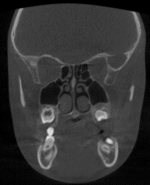

El CBCT (Cone Beam Computed Tomography) o tomografía volumétrica de haz cónico es una tecnología de imagen 3D que permite visualizar estructuras craneofaciales con altísima precisión.

A diferencia de una radiografía tradicional (2D), el CBCT:

- Captura volumen completo (3D)

- Permite ver hueso, dientes y vías aéreas

- Usa menor radiación que un TAC médico convencional

- Es ideal para diagnóstico funcional, estructural y anatómico

- Análisis nasal detallado

- Cornetes (hipertrofia)

- Desviación septal

- Válvula nasal (clave en tu enfoque)

Puedes objetivar obstrucción nasal funcional